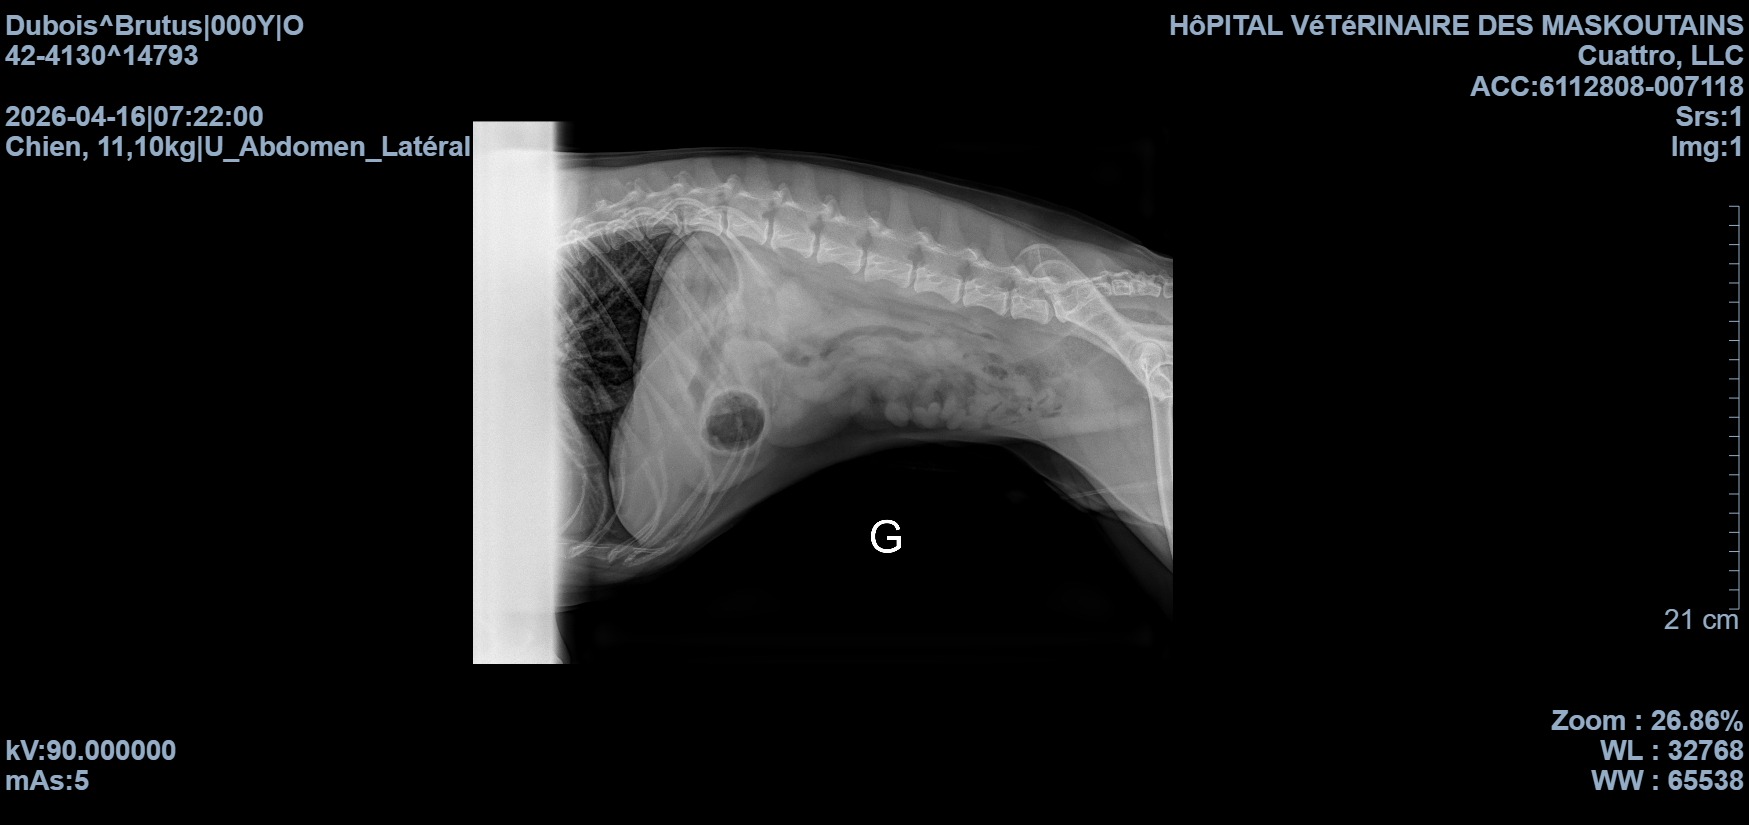

Mon entourage connaît tous mon petit clown de service, Brutus

Il y a deux jours, il nous a joué un très mauvais tour en mangeant des pistaches… avec les écailles. Malheureusement, cela a causé une obstruction et aujourd’hui, il a besoin d’une chirurgie d’urgence pour pouvoir rester avec nous encore de nombreuses années.

Cette opération est sa seule chance. Sans elle, sa vie est en danger.